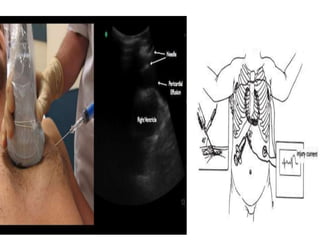

• Pericardiocentesis:

APPROACH

1. Sub-xiphoid :

A. Echo guided

B. ECG guided

C. Blind

2. Para-sternal

PERICARDIOCENTESIS

APPROACH 1. Sub-xiphoid : A.Echo guided B. ECG guided C. Blind 2. Para-sternal PERICARDIOCENTESIS